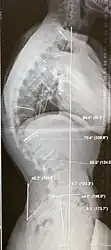

| Scheuermann's disease on lateral Xray of the T spine | |

Diagnosis is typically by medical imaging. The degree of kyphosis can be measured by Cobb's angle and sagittal balance.

-

Scheuermann's disease, showing various measurement of kyphotic/lordotic degrees and their supplementary angles. Notice the signature 'wedging' shape of the four vertebrae in the lower thoracic area. The other vertebral bodies are otherwise normal. -